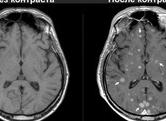

В основе парамагнитных контрастных веществ лежит редкоземельный элемент гадолиний. Контрастный препарат представляет раствор его водорастворимой соли, который вводится внутривенно и накапливается в областях с повышенным кровоснабжением (например, злокачественных опухолях). Из-за содержания редкоземельных элементов контрастное вещество относительно дорогое — цена одной дозы в 2010 году составляет 5000-10000 рублей. Ряд МРТ-исследований неинформативен без контрастного усиления. Первое парамагнитное контрастное вещество было создано фирмой Баер в 1988 году[1].